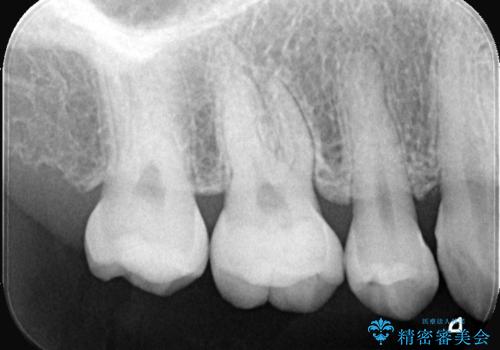

- 右上5番(小臼歯)の咬み合わせの面(咬合面)に小さな穴があることを主訴にご来院されました。視診およびレントゲン検査の結果、表面の穴は小さいものの、内部で虫歯が広がっていることが確認されました。患者様から「目立たないように治したい」というご希望があったため、健全な歯質を極力残しながら、審美性と耐久性に優れた**セラミックインレー(詰め物)**で修復する計画を立案しました。

治療ではまず、小さな穴から内部に広がっていた虫歯を、マイクロスコープ(歯科用顕微鏡)等を用いて精密に除去しました。虫歯を取り除いた後の空洞を整え、歯との適合性を高めるための精密な型取りを行いました。